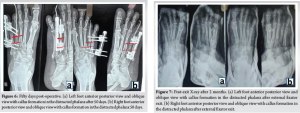

Post-operatively Immediate post op Xray taken followed by(Fig 4a,b) management with analgesics and antibiotics was started. Pin sites were regularly dressed to prevent post-operative infections. The patient was advised to be strictly non-weight bearing after surgery. Ten days post-operatively, the patient was given time for soft tissue healing and swelling to reduce. Distraction of the metatarsal was started with 0.25 mm twice daily. X-rays were taken every 10 days to check for callus formation, bone alignment, and MTPJ stability(Fig 5a,b). Distraction was conducted for 40 days, with X-ray showing regeneration of 2 cm along with callus and satisfactory arch of parabola connecting all metatarsal heads (Fig. 6a, b). The external fixator was removed after 2 months (Fig. 7a, b). After the fixator was removed and time was given for the callus to gain satisfactory strength, the patient was mobilized with full weight-bearing on day eighty[15].

Brachymetatarsia, though rare, can lead to both functional and esthetic concerns, especially when bilateral and symptomatic. The fourth metatarsal is the most frequently affected, and treatment is warranted in cases of pain, deformity, or patient-driven cosmetic dissatisfaction [1-3]. Among available surgical options, distraction osteogenesis is increasingly favored due to its ability to achieve gradual lengthening without bone grafts[12]. This method, originally described by Kawashima et al. allows for controlled soft tissue adaptation and minimization of neurovascular complications [16]. However, it carries risks, such as MTPJ subluxation, pin tract infection, and delayed union [9]. In our case, a modified technique using external rail fixators with axial trans-articular K-wire stabilization was employed. This approach ensured stability of the MTPJ during the distraction phase and helped maintain alignment of the regenerating segment, a modification supported by Peña-Martínez et al. who reported improved outcomes with joint stabilization during lengthening[13]. Compared to acute lengthening methods, which can achieve immediate correction but carry a higher risk of ischemia and graft complications [9], distraction osteogenesis enables more predictable biological regeneration[15]. Baek and Chung have shown that gradual distraction results in fewer complications and better cosmetic outcomes in multi-ray deformities[11]. Nonetheless, callotasis is not devoid of complications. Masada et al. documented pre-mature consolidation and MTPJ stiffness as frequent drawbacks[3]. Our use of a trans-articular K-wire likely contributed to the prevention of these issues in this case. Moreover, the incorporation of the Lelièvre metatarsal parabola concept guided the endpoint of distraction to restore functional forefoot geometry[10]. The results were clinically and radiologically satisfactory, with restored alignment, joint mobility, and complete resolution of the patient’s pain and deformity. No MTP subluxation, pin site infection, or hardware failure was observed, aligning with outcomes reported by Shim and Park [12]. This technique presents a reproducible and safe alternative for managing bilateral brachymetatarsia, particularly in young adults with high cosmetic expectations and good bone healing potential.

The patient’s primary complaint of pain was treated as the parabolic arch of the metatarsal head (Fig. 8a, b and 9a, b-b) was restored, along with a lengthening of 2 cm. After removal of the external fixator (Fig. 10a, b, c, d), the patient was pain-free and functionally restored.